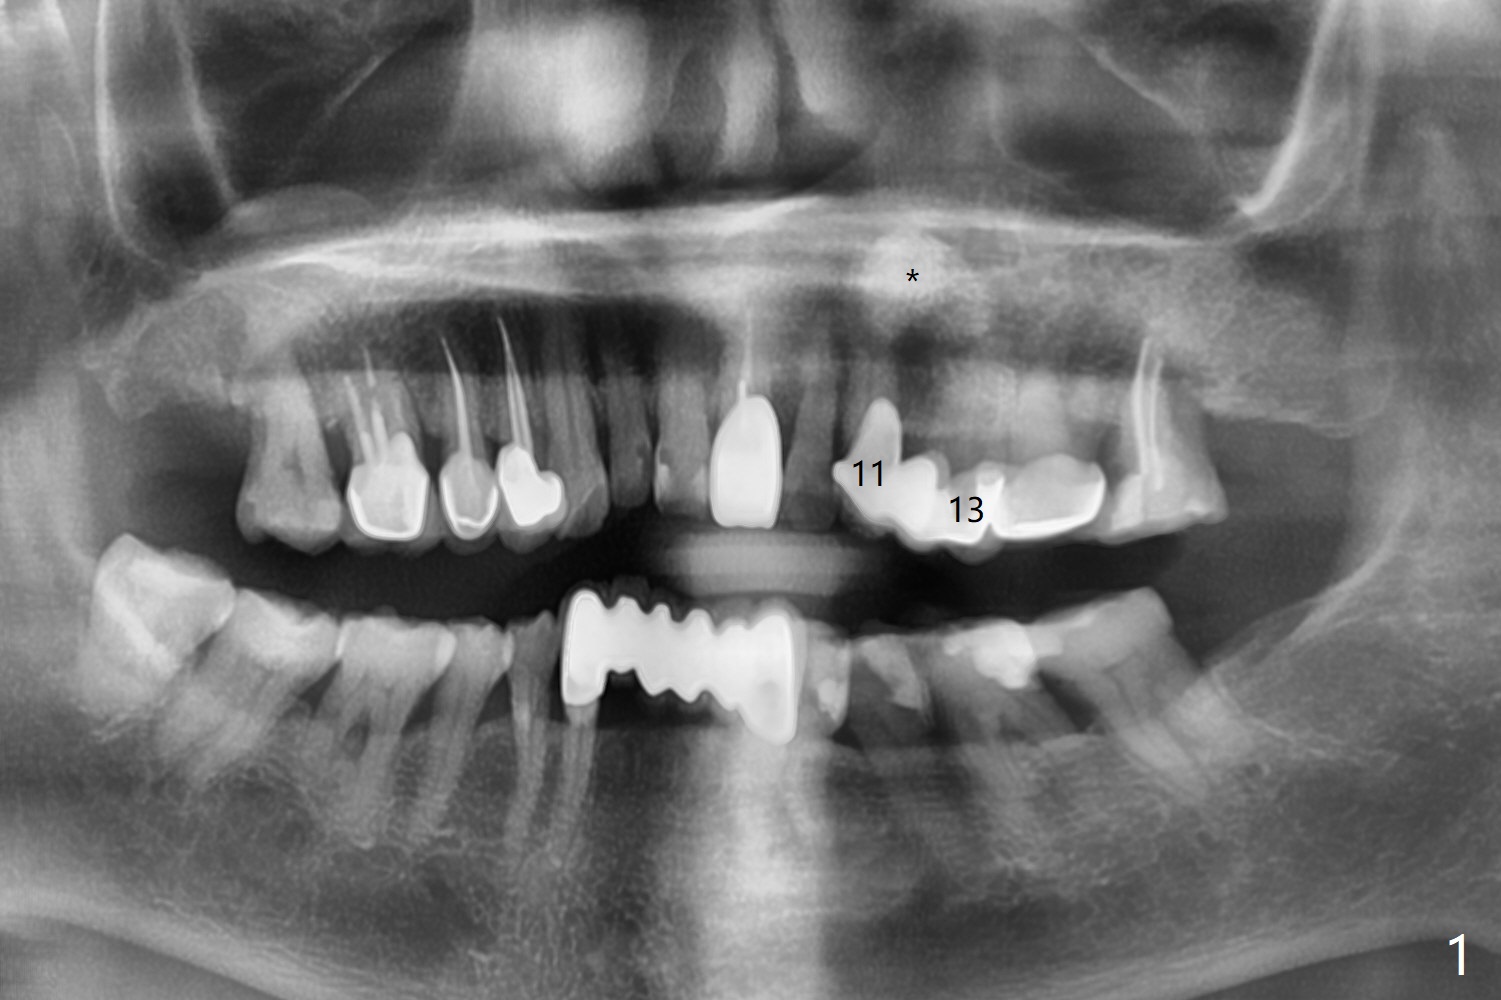

A 73-year-old woman has had discomfort with the upper left FPD for long time (Fig.1). A large asymptomatic fistula is found recently above the pontic with a small superior pedicle (Fig.2,3 <). CT shows radiopaque (Fig.1,4 *) and radiolucent (Fig.4 >) lesions are associated with the tooth #13, instead of the tooth #11.